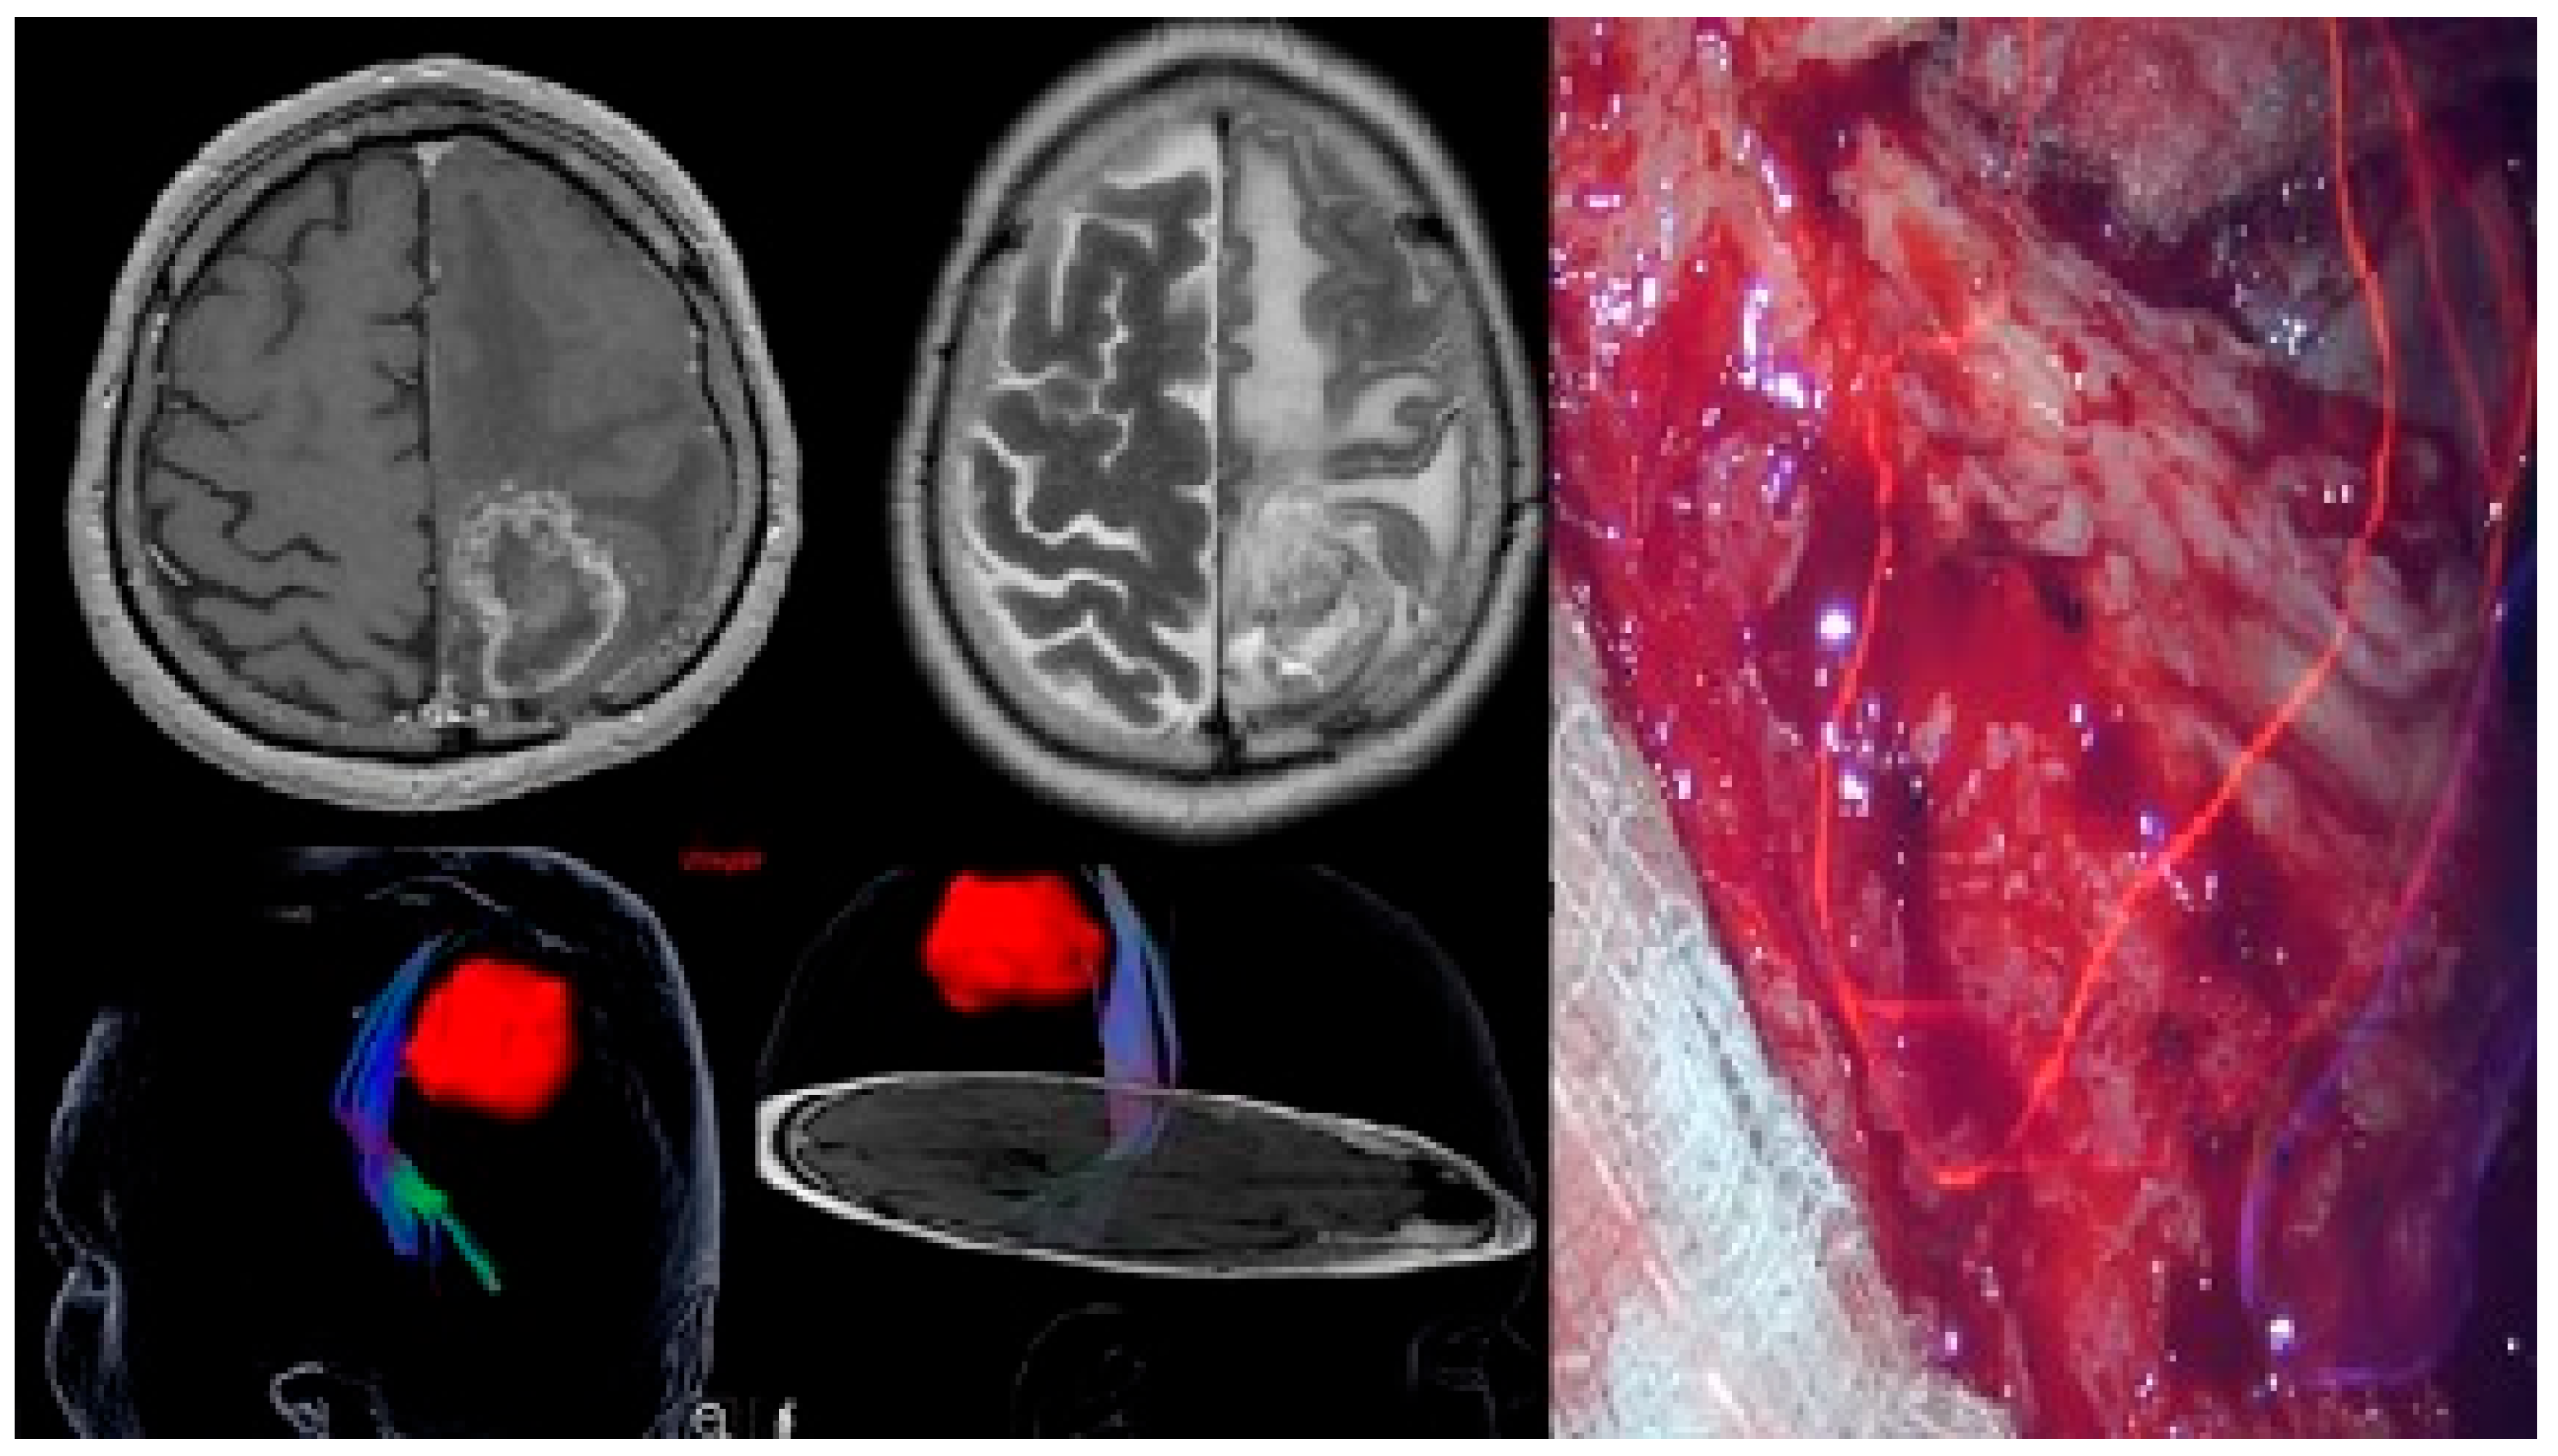

2.5. Neuroimaging Evaluation

2.7. Surgical Management

3.3. Tumor Characteristics